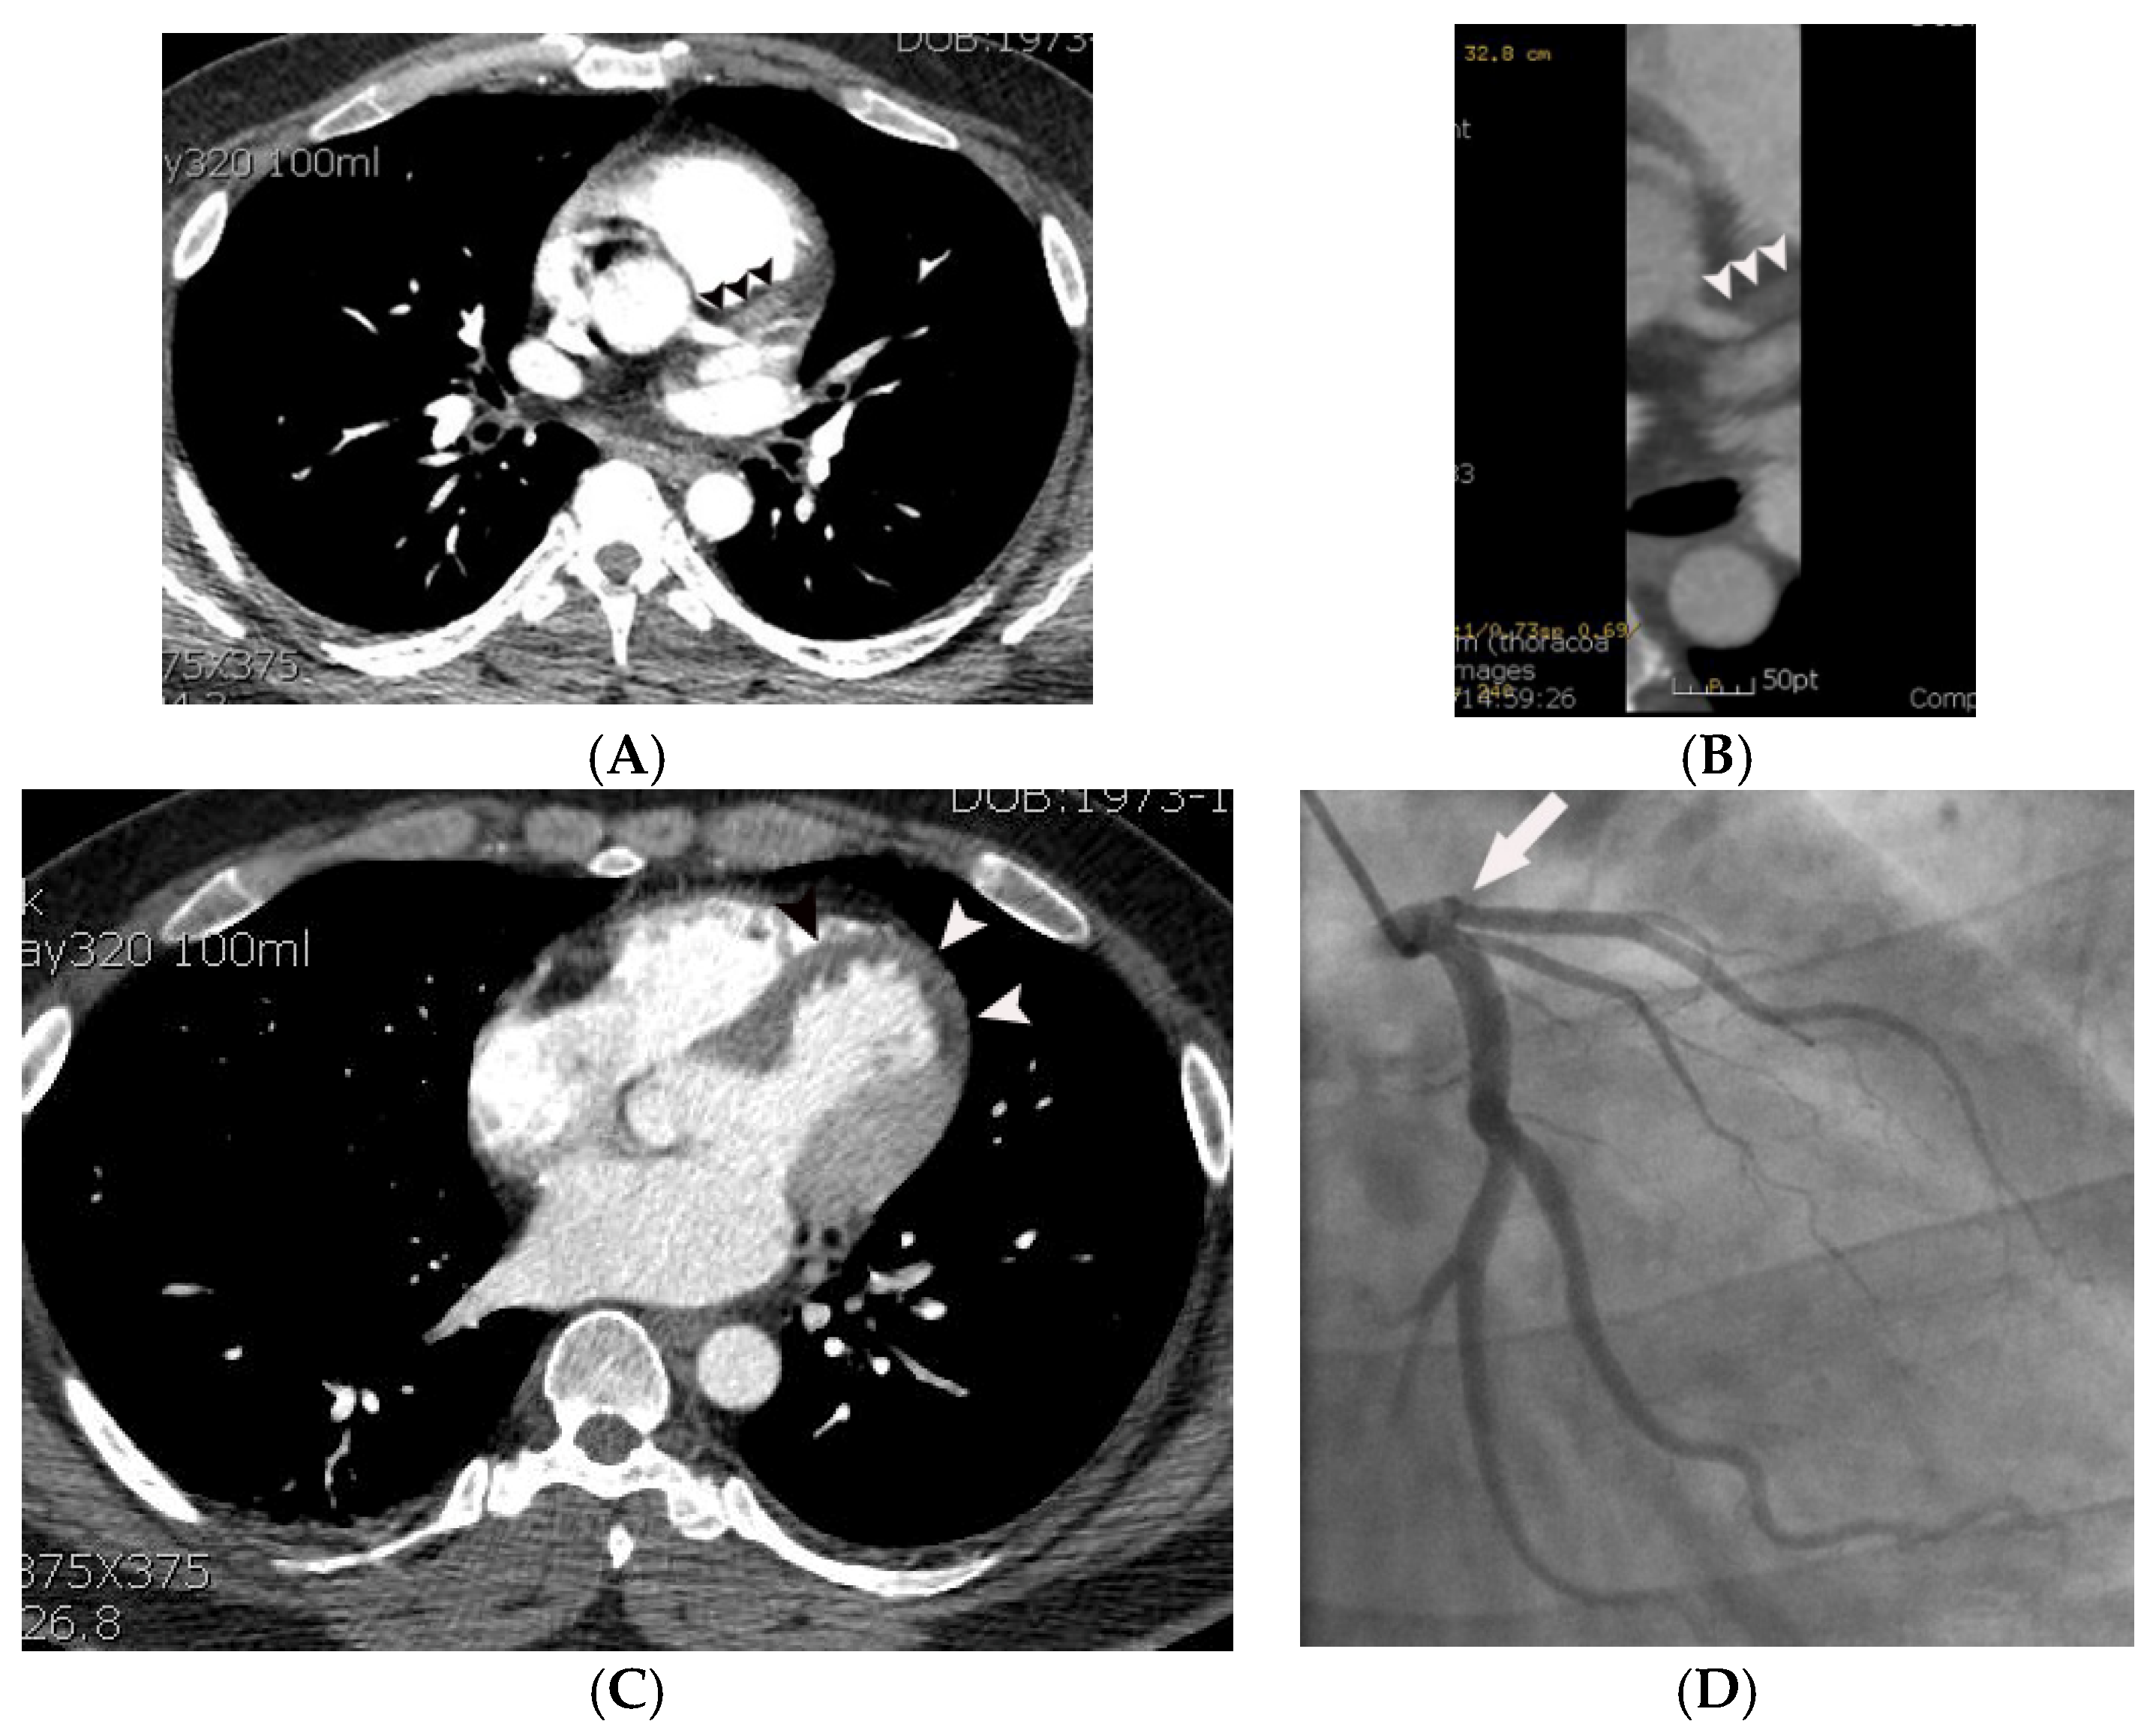

Figure 1.

Representative case, demonstrating probable MPD in a 69-year-old male with acute chest pain. Subendocardial or transmural hypoattenuation (arrowheads in (A–C)) was demonstrated on the multiple non-gated axial CT images along the left anterior descending coronary territory (i.e., antero-septum and the left ventricular apex). Note that attenuation of the mid-left anterior descending coronary artery (arrow in (D)) is low compared to the right coronary artery and left circumflex coronary artery (arrowheads in (D)), suggesting critical narrowing or occlusion of the left anterior descending coronary artery. Critical narrowing in the proximal left anterior descending coronary artery was confirmed on subsequent coronary angiography (arrow in (E)).